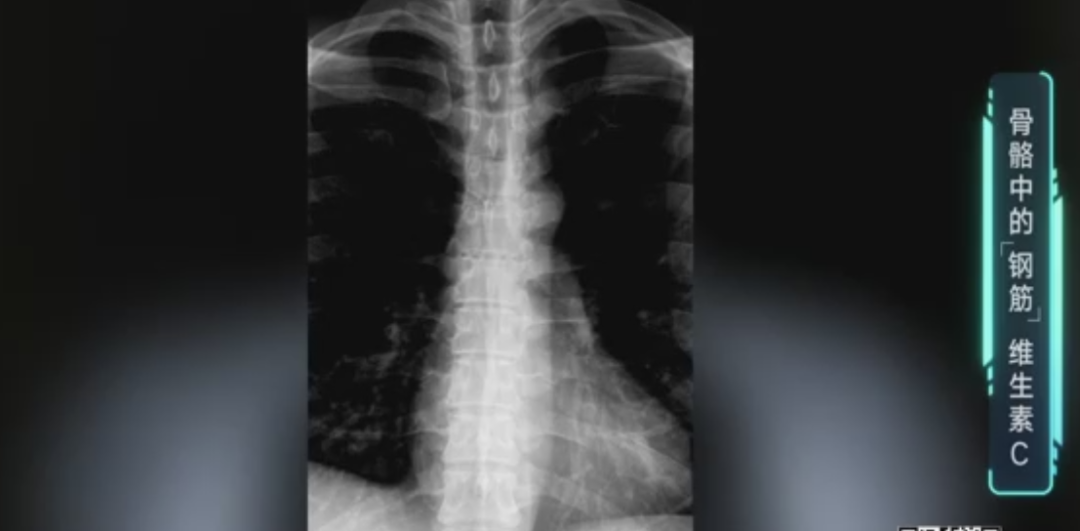

如果身体是一幢高楼大厦

骨骼就是构建楼宇的钢筋

现在,许多老年人基本上动脉都钙化、骨化得很厉害,因为没有好好补充维生素C,所以钙在身体里“乱窜”,并沉积到其他地方去了。